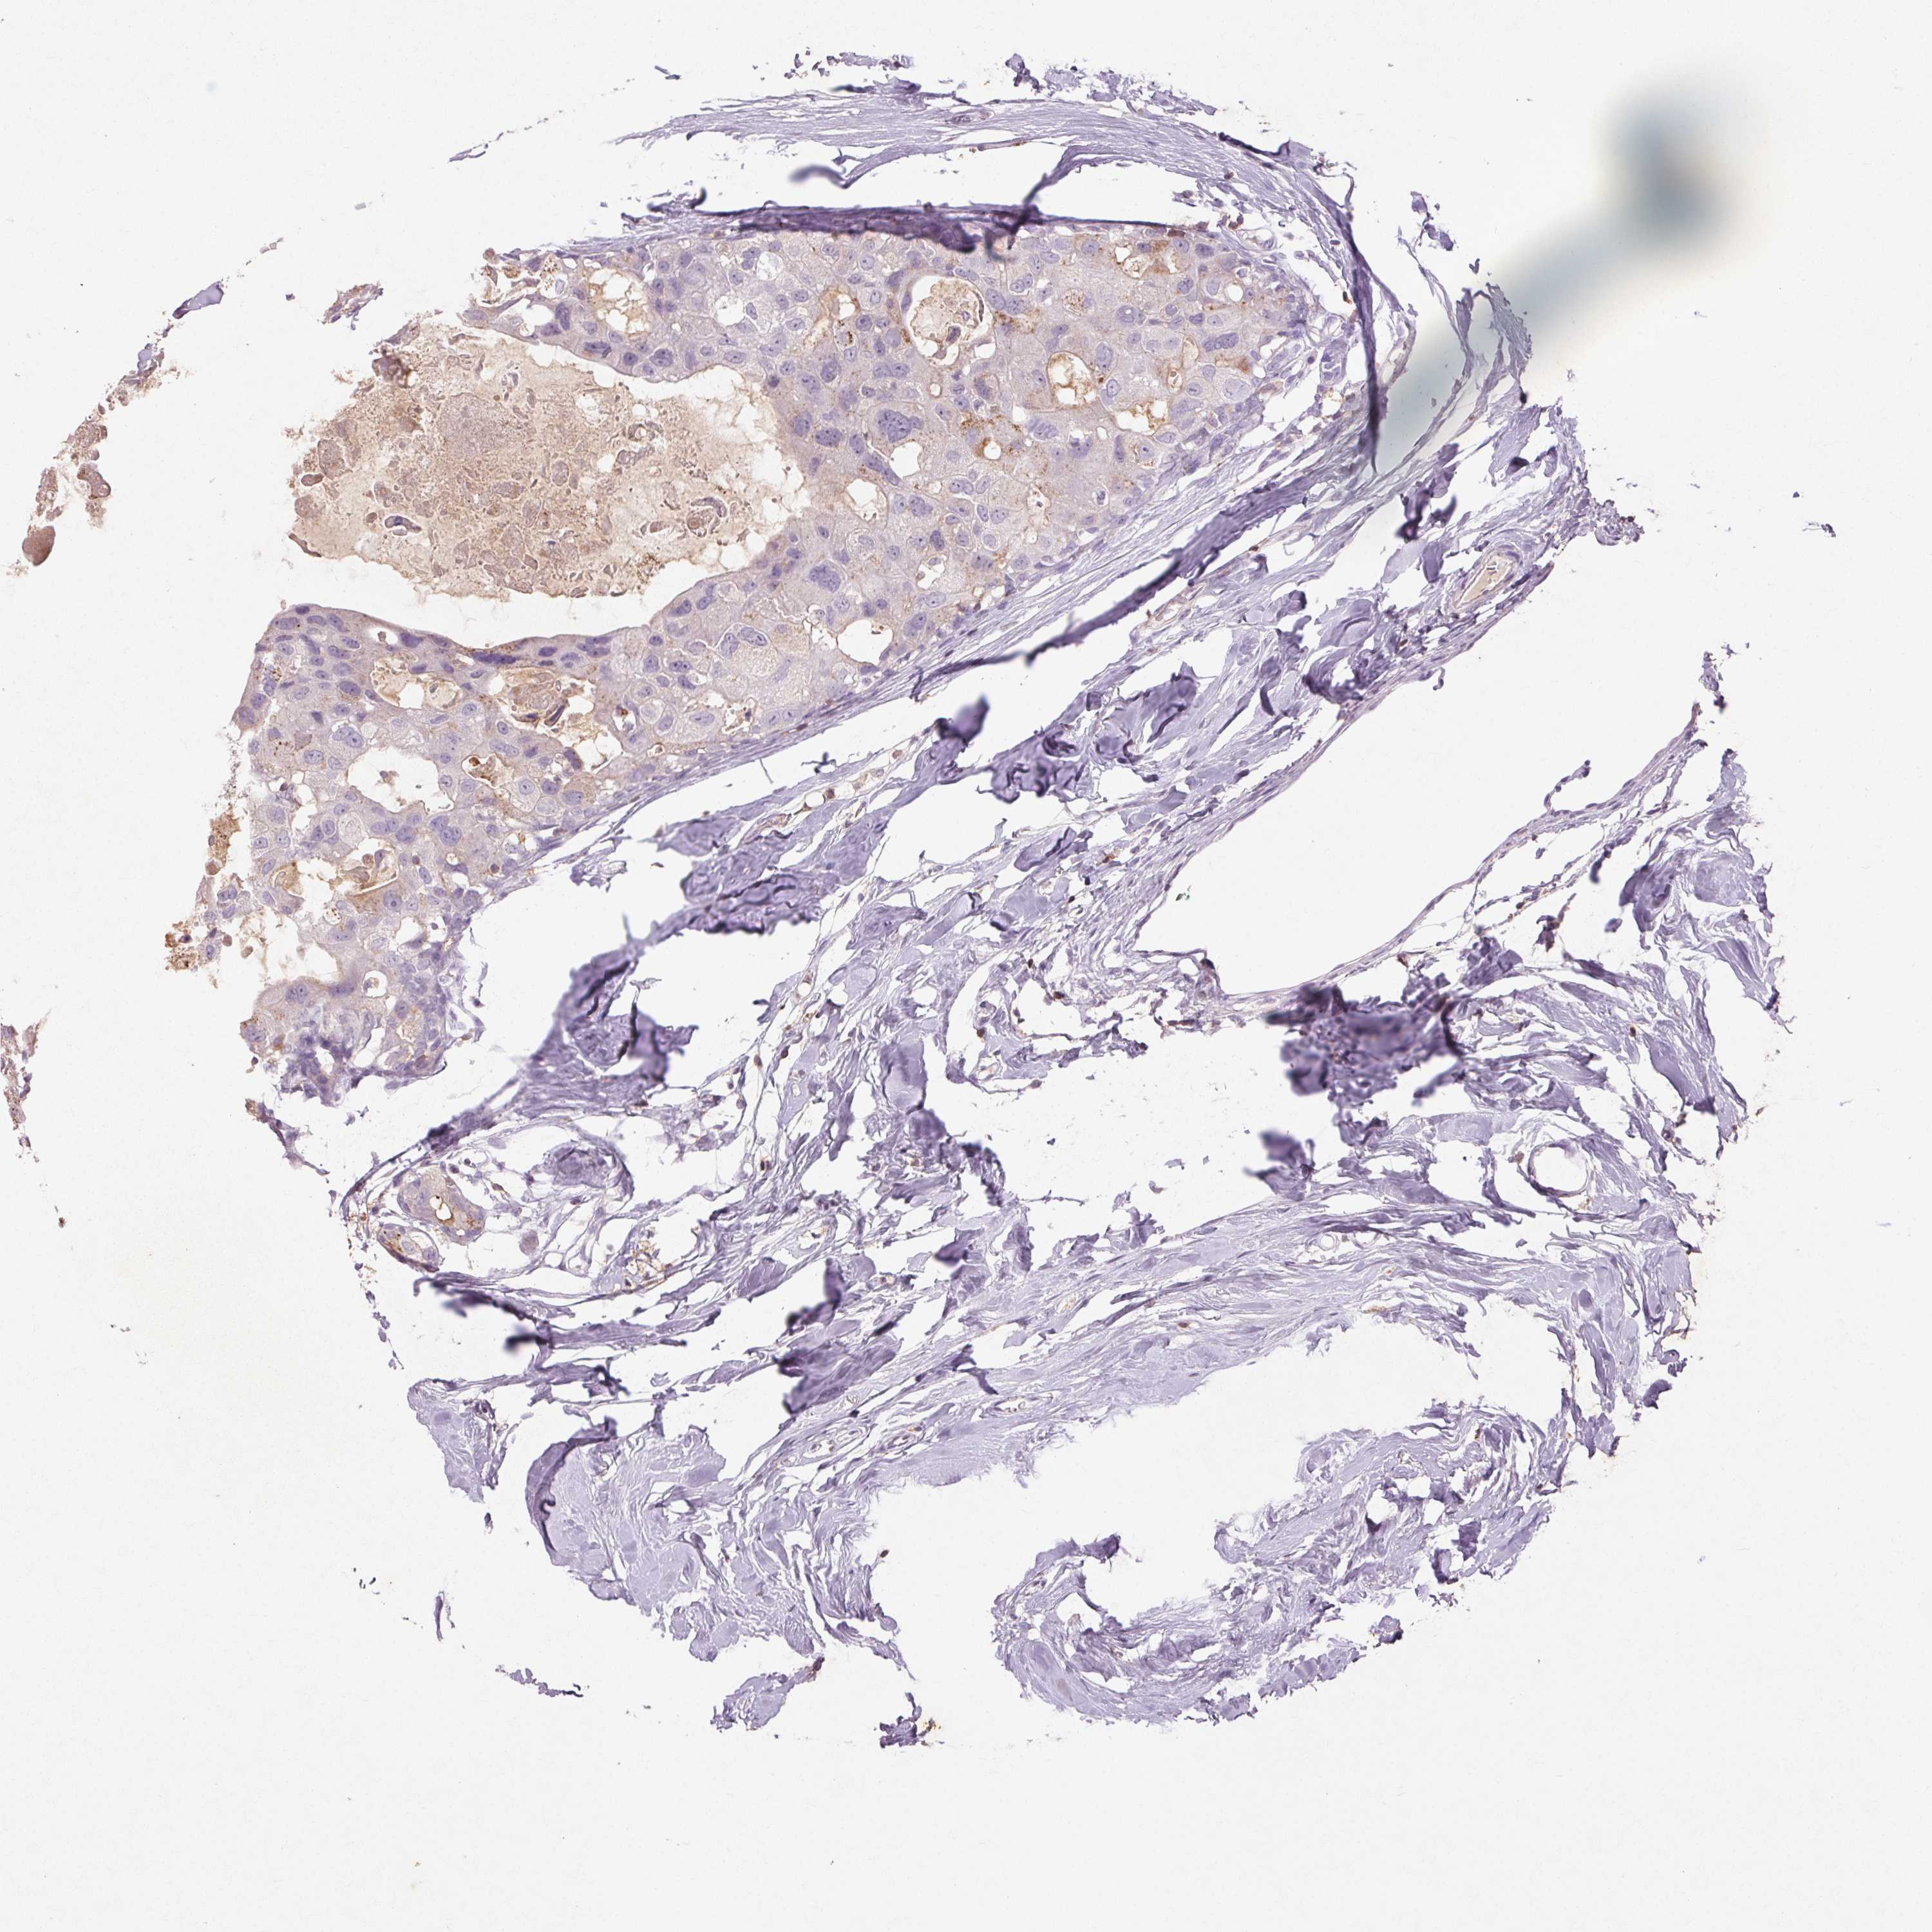

CANCER BREAST CANCER Show tissue menu

BRCA TCGA BRCA VALIDATION PROTEIN EXPRESSION

Breast cancer

Human cancer

FNDC7 is not prognostic in Breast Invasive Carcinoma (TCGA)